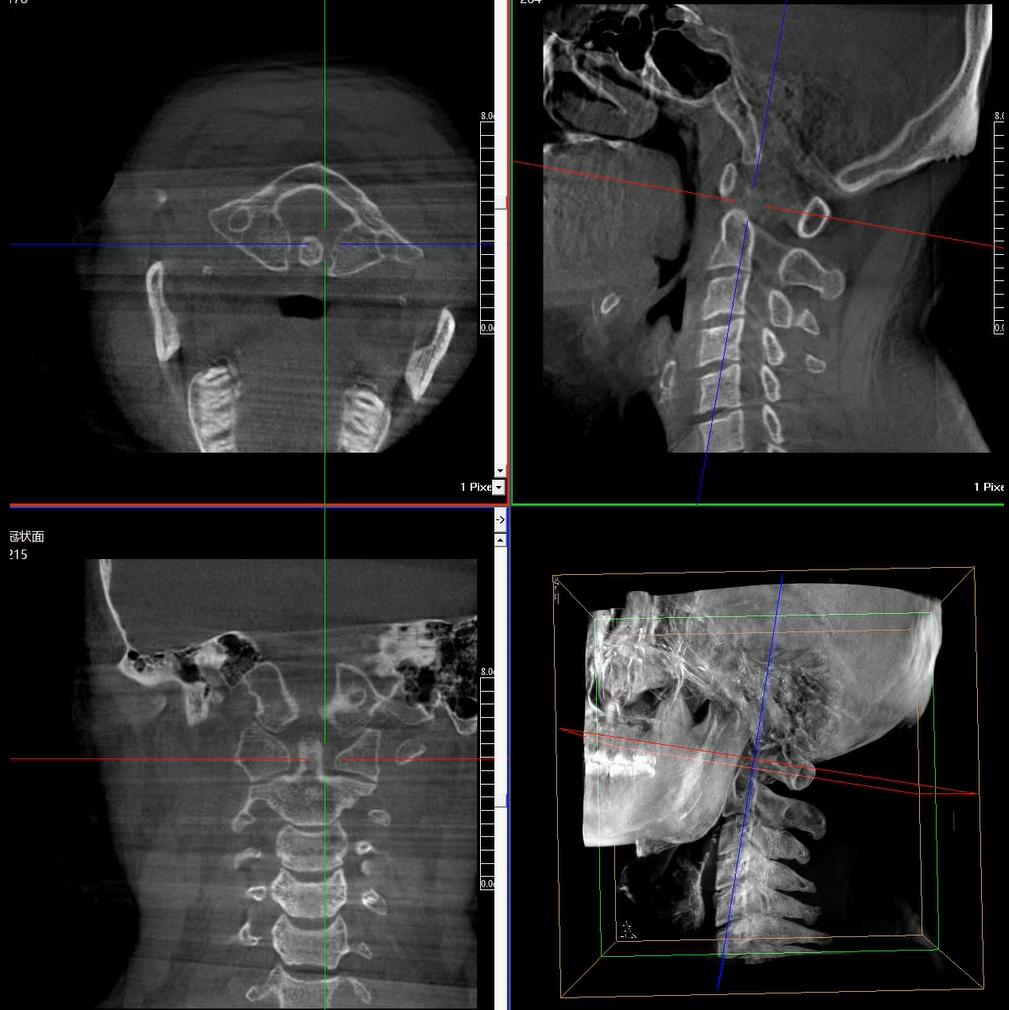

術(shù)中三維成像和橫斷面圖像提供多角度的手術(shù)診斷信息,輔助醫(yī)生進(jìn)行術(shù)中評估判斷,諸如骨折復(fù)位情況和內(nèi)植入螺釘?shù)某叽绾臀恢?,輔助手術(shù)更好地完成。

提供更大的術(shù)中三維成像視野,采集更多圖像信息,可一次拍全全段頸椎、全段腰椎、七節(jié)胸椎、雙側(cè)骶髂關(guān)節(jié)、股骨頭及單側(cè)盆骨。